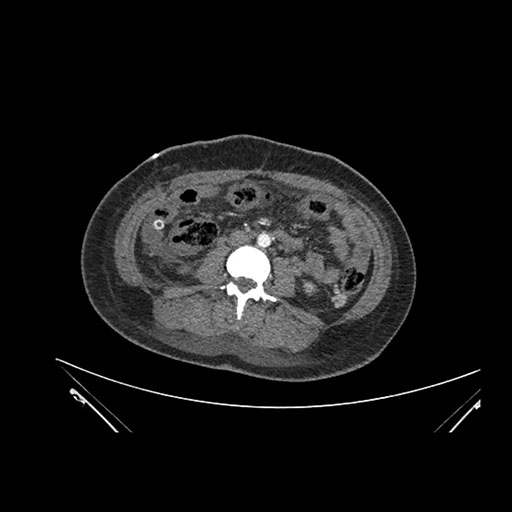

Imaging Analysis

Look through the patient's CT scan to identify any areas of concern for the necessary procedure.

Coronal Venous